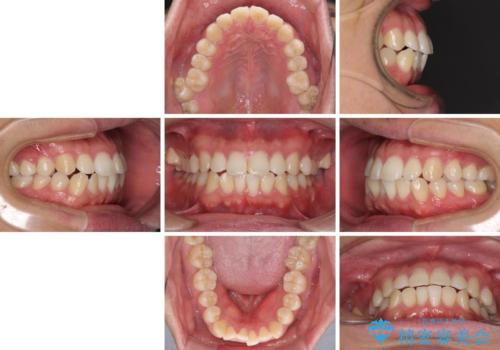

インビザラインで奥歯の咬み合わせと前歯のデコボコを改善

- 前歯のデコボコと奥歯の咬み合わせを気にして来院された患者様です。

前歯のデコボコはインビザラインで十分に対応可能と判断できましたが、咬合力が強いため、臼歯(特に右側)の交叉咬合はインビザライン単体では困難と思われました。

インビザライン単体では右側の交叉咬合を解消することができなかったため、アンカースクリューを併用して咬合を改善させました。